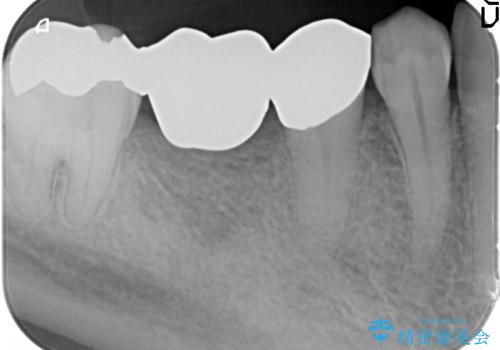

矯正治療後、右下のインレーブリッジおよび左下の銀歯のやりかえを行なっています。

右上の八重歯は、右上の奥歯を矯正用ミニスクリューを用いて遠心移動を行い解消しました。